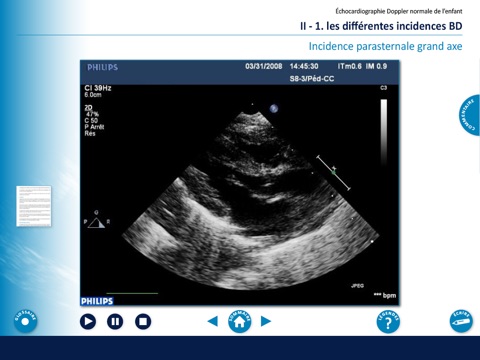

Echocardiographie chez l'enfant

Abord de léchocardiographie Doppler chez lenfant dans son aspect normal mais aussi pathologique (CIV, Transposition des gros vaisseaux, CIA, Persistance du canal artériel, HTAP, Obstacles du cœur gauche), sous légide de la Filiale de Cardiologie Pédiatrique Congénitale de la Société Française de Cardiologie.